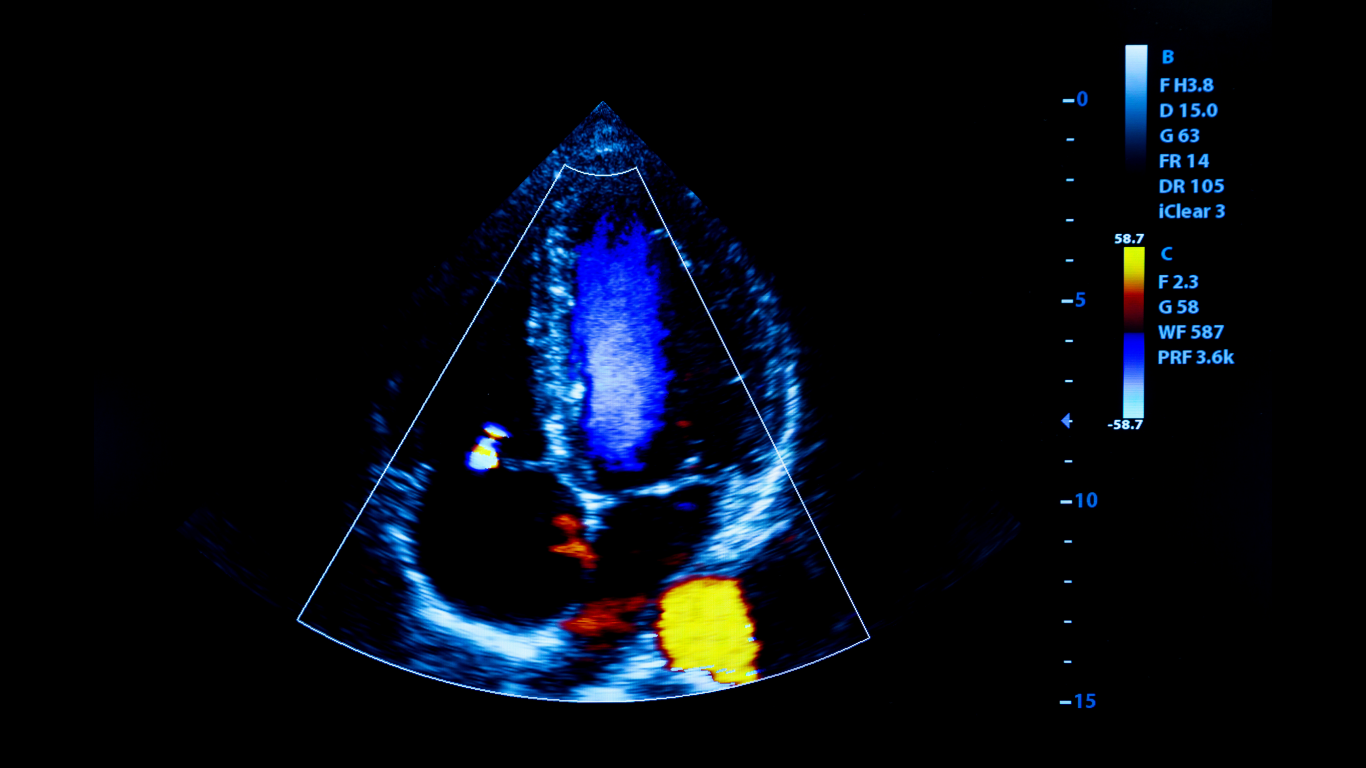

O ecocardiograma transtorácico é um exame de imagem que permite avaliar a estrutura e o funcionamento do coração. Ele utiliza ondas sonoras para criar imagens

O coração é um dos órgãos mais importantes do corpo, e monitorar seu funcionamento é essencial para a saúde. O ecocardiograma transtorácico é um exame

O eco transtorácico, também conhecido como ecocardiografia transtorácica, é um exame não invasivo fundamental para avaliar a saúde do coração. Indicado tanto para atletas quanto